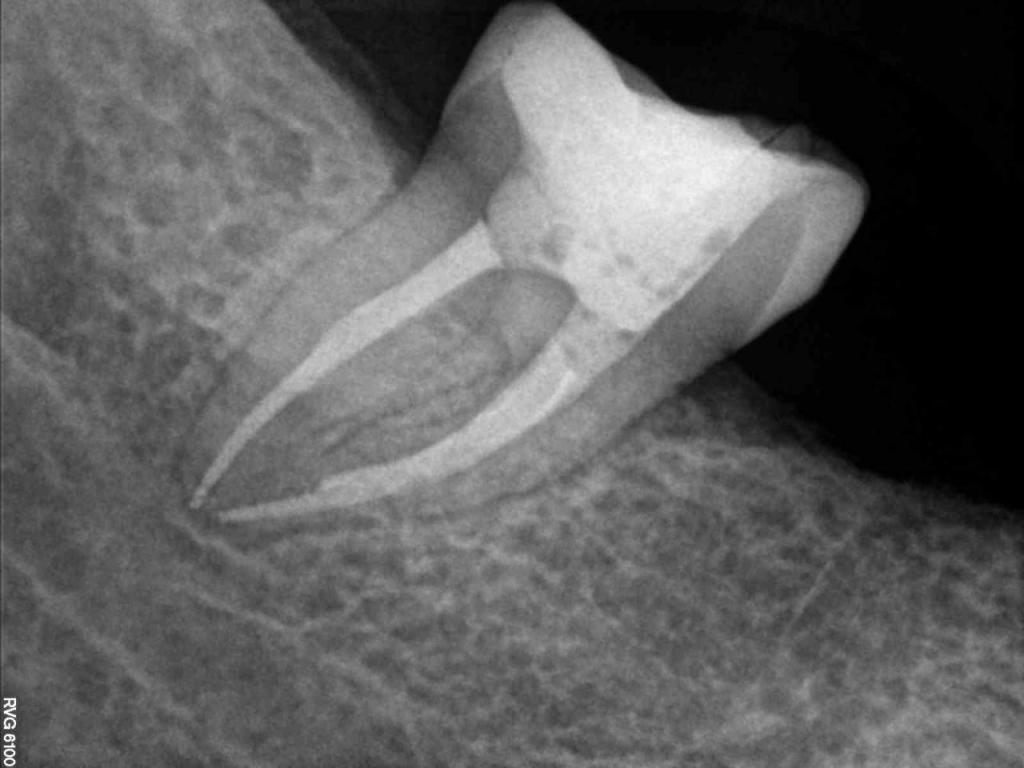

Although the primary use of visual documentation is for patient charts, dental images provide a meaningful way to communicate with patients about their care needs. Digital imagery is a vital tool for educating patients and an essential way to share information with office staff, colleagues and referring doctors. Digital technology has allowed Southcenter Endodontics to enhance our practice and improve the delivery of care to our patients. Below you will see images of “Before” and “After” scenarios. By clicking on a thumbnail image below, you will be able to see and a larger view of the x-ray taken at Southcenter Endodontics and notations made regarding each film.